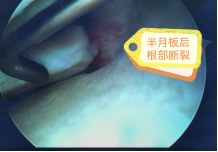

运动医学:肩袖损伤、肩关节脱位、钙化性肌腱炎、膝关节前后交叉韧带损伤、内侧副韧带损伤、内外侧半月板损伤、复发性髌骨脱位、髋关节撞击综合征、肘关节僵硬、慢性踝关节不稳等疾病的微创关节镜手术治疗。